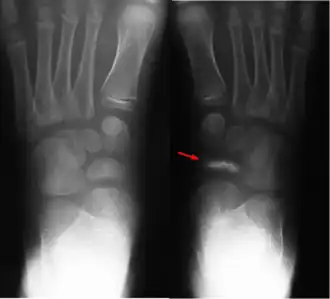

Болезнь Кёллера I — хроническое дистрофическое заболевание ладьевидной кости стопы, приводящее к её асептическому некрозу.

Причина асептического некроза у детей объясняется нарушением процесса окостенения ладьевидной кости. Что подтверждается на рентгенограммах: отмечается сплющивание, фрагментизация ядра окостенения, увеличение межкостного пространства, отделяющего ладьевидную кость от таранной и клиновидной.